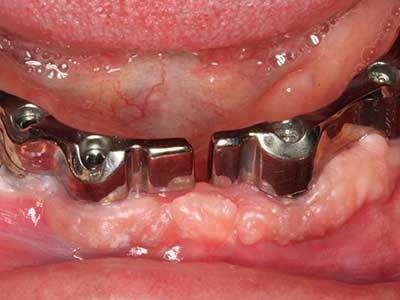

Aplicación: Terapia periodontal

En pacientes de edad avanzada, las enfermedades periodontales marginales representan la razón principal por la que es preciso realizar una extracción. Estas enfermedades tienen principalmente su causa en una colonización bacteriana de la bolsa periodontal y en la inflamación que esta provoca, lo que da lugar a una pérdida del ligamento periodontal. La formación de biopelículas y concreciones subgingivales representa un factor etiológico decisivo para la degradación ósea marginal, por lo que su eliminación cobra una importancia especial en la terapia (Drisko 2014, Plessas 2014).

En el tratamiento de una periodontitis se hace una diferenciación entre la fase inicial y la fase quirúrgica. Además de la instrucción y la motivación entorno a la higiene bucal, en ambas fases debe realizarse una limpieza apropiada de la superficie radicular; a este respecto, en el tratamiento regenerador se elige casi siempre un acceso abierto. La superficie radicular también puede limpiarse mediante piezocirugía utilizando piezas especiales, pues el uso de insertos de diferentes curvaturas permite llegar a zonas de difícil acceso, como son las furcaciones. En esta técnica, la refrigeración interna de agua del sistema ayuda a retirar las concreciones y las bacterias disueltas de la bolsa periodontal. Por otro lado, para reducir a un mínimo la eliminación de la sustancia dental dura, en los sistemas especiales como el Piezomed se ha incorporado una aplicación con retroalimentación. En este caso, según se ejerza más presión sobre la pieza periodontal, la potencia de eliminación se reduce.